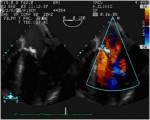

Immagine82-107x150-(1).jpg Immagine92-150x120.jpg

Insufficienza mitralica di tipo I, dovuta a dilatazione anulare e relativa immagine all’eco-colordoppler